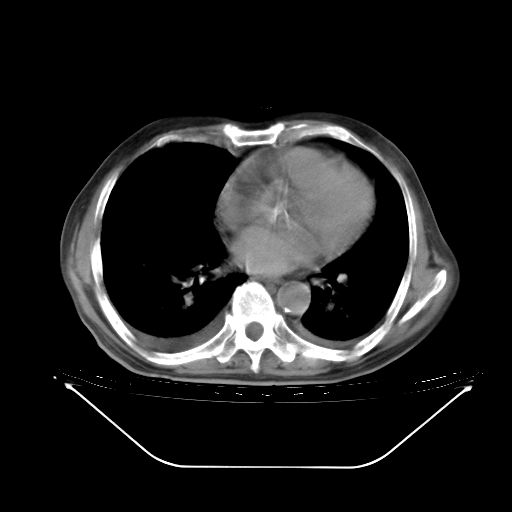

胸腹部CT,诊断意见:左上肺叶钙化灶、左侧胸膜局限性增厚并钙化、胆囊炎。描述部分肺组织呈磨玻璃样改变。

今天复查肺部CT,发现双肺广泛磨玻璃样改变。所以我把3月19日和5月9日相隔50天的肺部CT上传。请大家会诊。

2009年3月19日肺部CT片。

5月9日肺部CT(在4月27日齐鲁医院肺部CT描述部分肺组织磨玻璃样改变,12天后肺组织广泛磨玻璃样改变)

大致读了系列胸部CT:纵隔窗无明显异常,肺窗:从4、27至今:主要是双肺中下野外带可见毛玻璃样改变,目前处于急性肺泡炎阶段,至于原因考虑1、结替组织或胶原血管性疾病所致?2、恶性疾病如恶组在肺部所致的表现或细支气管肺泡癌?3、药物或其它原因如肺蛋白沉着症所致肺泡炎目前不太可能?总之,明天就去请我院的呼吸科、感染科、血液科和临免专家会诊哈。